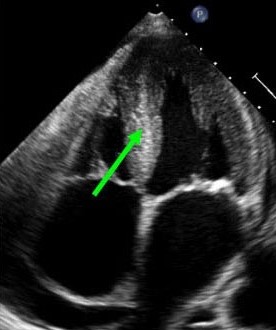

Obraz amyloidozy serca w badaniu echokardiograficznym (zaznaczona pogrubiona przegroda międzykomorowa)Obraz amyloidozy serca w badaniu echokardiograficznym

(zaznaczona pogrubiona przegroda międzykomorowa)

Echokardiografia, czyli ultrasonograficzna ocena serca, to obecnie „złoty standard” w rozpoznawaniu amyloidozy serca. Nacieczenie amyloidem nadaje charakterystyczny wygląd mięśnia sercowego, który został opisany jako „iskrzące się ziarnistości” (zwiększona echogeniczność). W amyloidozie dochodzi do pogrubienia jego ścian, co daje obraz koncentrycznego (dośrodkowego) przerostu mięśnia, szczególnie w obrębie przegrody międzykomorowej, przy braku współistniejącego nadciśnienia tętniczego w wywiadzie. Jednak w rzeczywistości w amyloidozie masa mięśnia sercowego nie powiększa się, ponieważ amyloid odkładany jest w przestrzeniach miedzykomórkowych. Frakcja wyrzutowa (z angielskiego: enjection fraction- EF) jest zwykle prawidłowa, z zachowaną czynnością skurczową, co odróżnia tę chorobę od wielu innych rodzajów niewydolności krążenia. Obserwuje się natomiast zaburzenia napełniania komór (zwłaszcza prawej), wynikające z upośledzonego rozkurczu mięśnia sercowego. Niewydolność rozkurczowa jest typowa dla amyloidozy, nawet we wczesnym okresie zajęcia serca. Upośledzenie funkcji skurczowej lewej komory rozpoznaje się rzadko i wyłącznie w zaawansowanym okresie choroby. Pogrubienie płatków zastawek oraz obecność płynu w worku osierdziowym uzupełnia obraz zmian echokardiograficznych w amyloidozie serca.